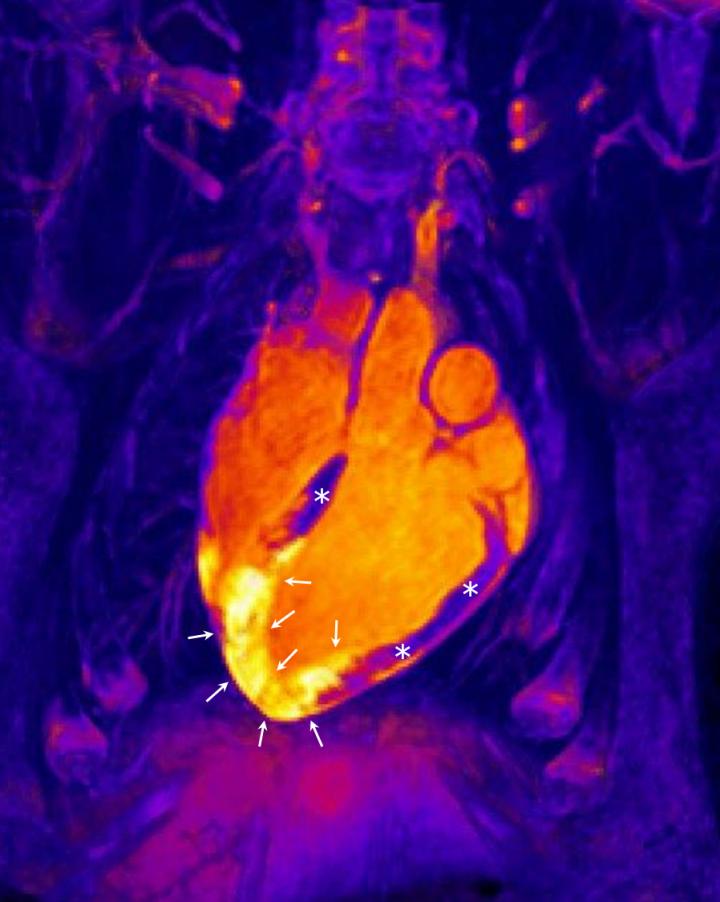

For many years, scientists have assumed that a heart attack is followed immediately by an inflammatory response featuring increases in water content and cellular infiltration and that this response remains stable for at least 1 week and then progressively dissipates. Two years ago, the research team behind the new studies published a series of animal studies that challenged this view, but the most important challenge remained: to validate the new findings in human patients. The new studies used the most advanced magnetic resonance imaging (MRI) technology to demonstrate that the human heart produces 2 well-differentiated edematous reactions occurring at distinct times after an infarction. These results have immediate clinical implications for ongoing clinical trials and could form the basis of future studies focused on the specific modulation of each of these independent edematous phases.

The study is the first in the world to study heart attack patients by MRI so soon after the re-establishment of blood flow. In addition to studies in patients, the team have also extended their investigation of infarction in pigs, the experimental model most similar to humans. The unique translational research infrastructure at the CNIC includes identical imaging equipment for human and animal studies, allowing the team to demonstrate that treatments during an infarction can change the composition of the cardiac muscle during the first hours after reperfusion, resulting in a much more rapid recovery of the heart. In the words of Dr. Fernández-Jiménez, "MRI provides an extraordinary ability to noninvasively visualize events occurring after an infarction in real time, including inflammation, tissue volume expansion, hemorrhage, and obstruction of the microcirculation."